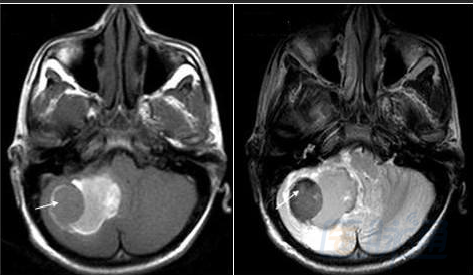

然后解决第三个问题,轻松一下,图来啦,让我们巩固一下今天学习的成果,均为先T1,后T2。

慢性期(14d):

箭头